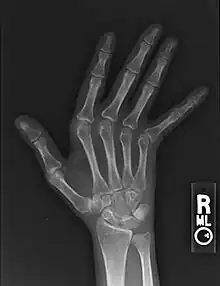

| Jaccoud arthropathy seen on a hand x-ray. As opposed to arthropathy due to rheumatoid arthritis, there are no erosions. | |

Jaccoud arthropathy (JA), is a chronic non-erosive reversible joint disorder that may occur after repeated bouts of arthritis.[1][2] It is caused by inflammation of the joint capsule and subsequent fibrotic retraction, causing ulnar deviation of the fingers, through metacarpophalangeal joint (MCP) subluxation,[1][3] primarily of the ring and little-finger.[3] Joints in the feet, knees and shoulders may also get affected.[1] It is commonly associated with systemic lupus erythematosus (SLE), and occurs in roughly 5% of all cases.[1][2]

Plain hand radiographs typically show marked ulnar subluxation and deviation at the metacarpophalangeal joints. Absence of erosions is a notable feature, although occasionally "hook" erosions may be observed, which are similar to those seen in SLE and ankylosing spondylitis. Evidence of muscle (soft tissue) atrophy also may be present.